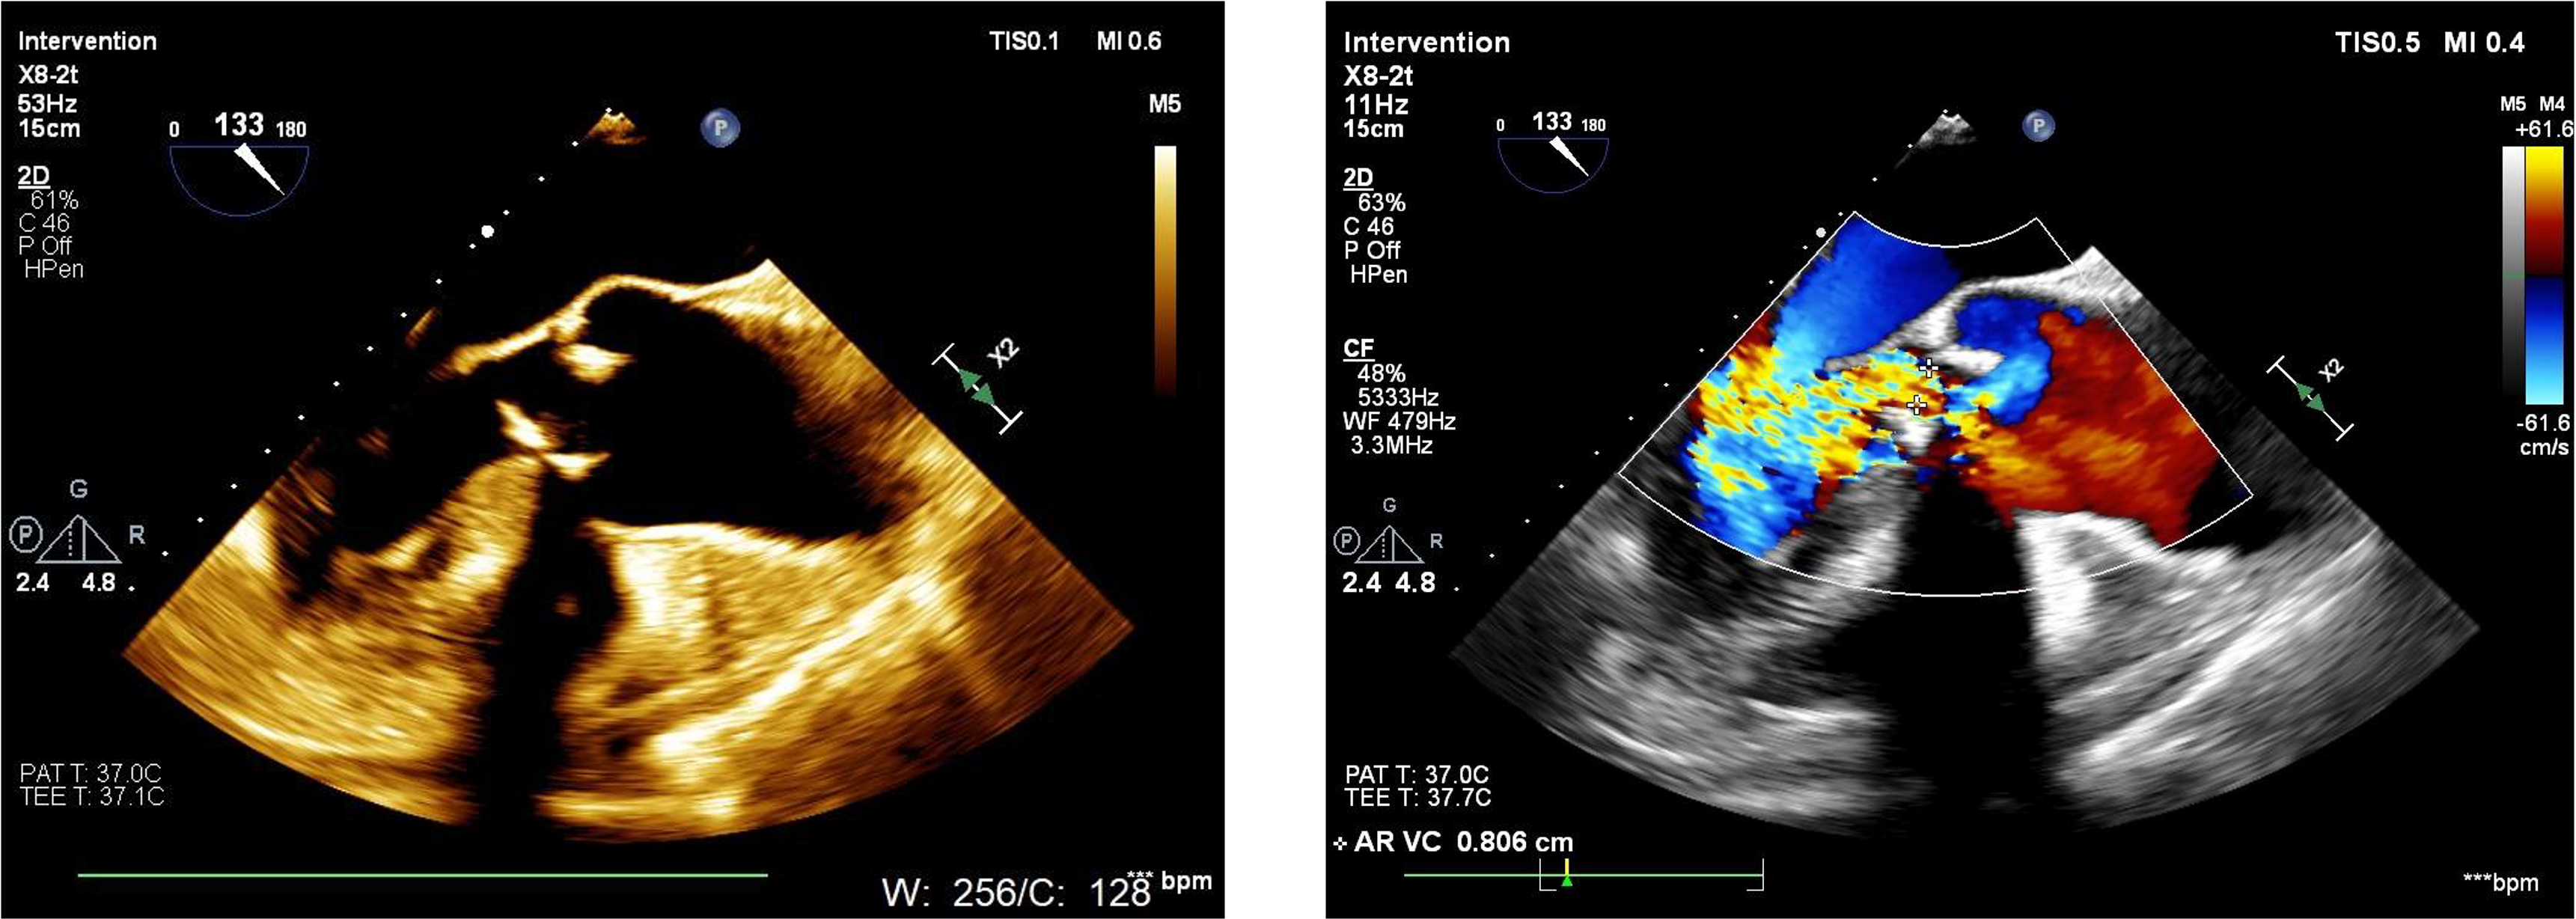

2D echo suggestive of severe aortic regurgitation. CT analysis done and we decided to opt for 24mm TAVR valve

SEV 24mm. was deployed and during reheathing patient developed circulatory collapse.